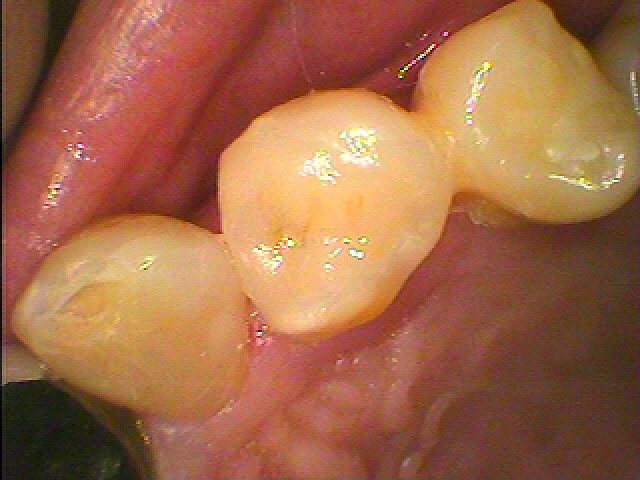

銀歯を外して白いセラミックに置き換えていきます|お知らせ |広島市安佐南区の歯科医院 銀歯を外して白いセラミックに置き換えていきます トップ お知らせ・ブログ お知らせ 銀歯を外して白いセラミックに置き換えていきます 銀歯を外して白いセラミックに置き換えていきます こんな銀歯が入っています 銀歯を外すと、虫歯があります かなり大きな虫歯があります かなり神経が近いです 横も詰めていきます CRにて覆罩をしていきます 綺麗なセラミックが入りました Web診療予約 初めての方へ 選ばれ続ける理由 院内設備について 歯が痛いしみる一般歯科 歯がぐらぐらする歯周病 健康な歯を保ちたい予防歯科 子供の虫歯予防をしたい小児歯科 銀歯をセラミックに審美歯科 白い歯を目指しませんか?ホワイトニング 矯正専門医がいるので安心矯正歯科 抜けた歯を補いたいインプラント・入れ歯 医院案内 スタッフ紹介 メリィハウス歯科クリニックオフィシャルホームページ ラベンダー歯科クリニックオフィシャルホームページ お知らせ・ブログ ホーム 診療科目 一般歯科 歯周病治療 予防治療 小児歯科 審美治療 ホワイトニング 矯正歯科 入れ歯・インプラント マウスピース矯正 初めての方へ 院長・スタッフ 設備紹介 医院案内・アクセス メニューを閉じる